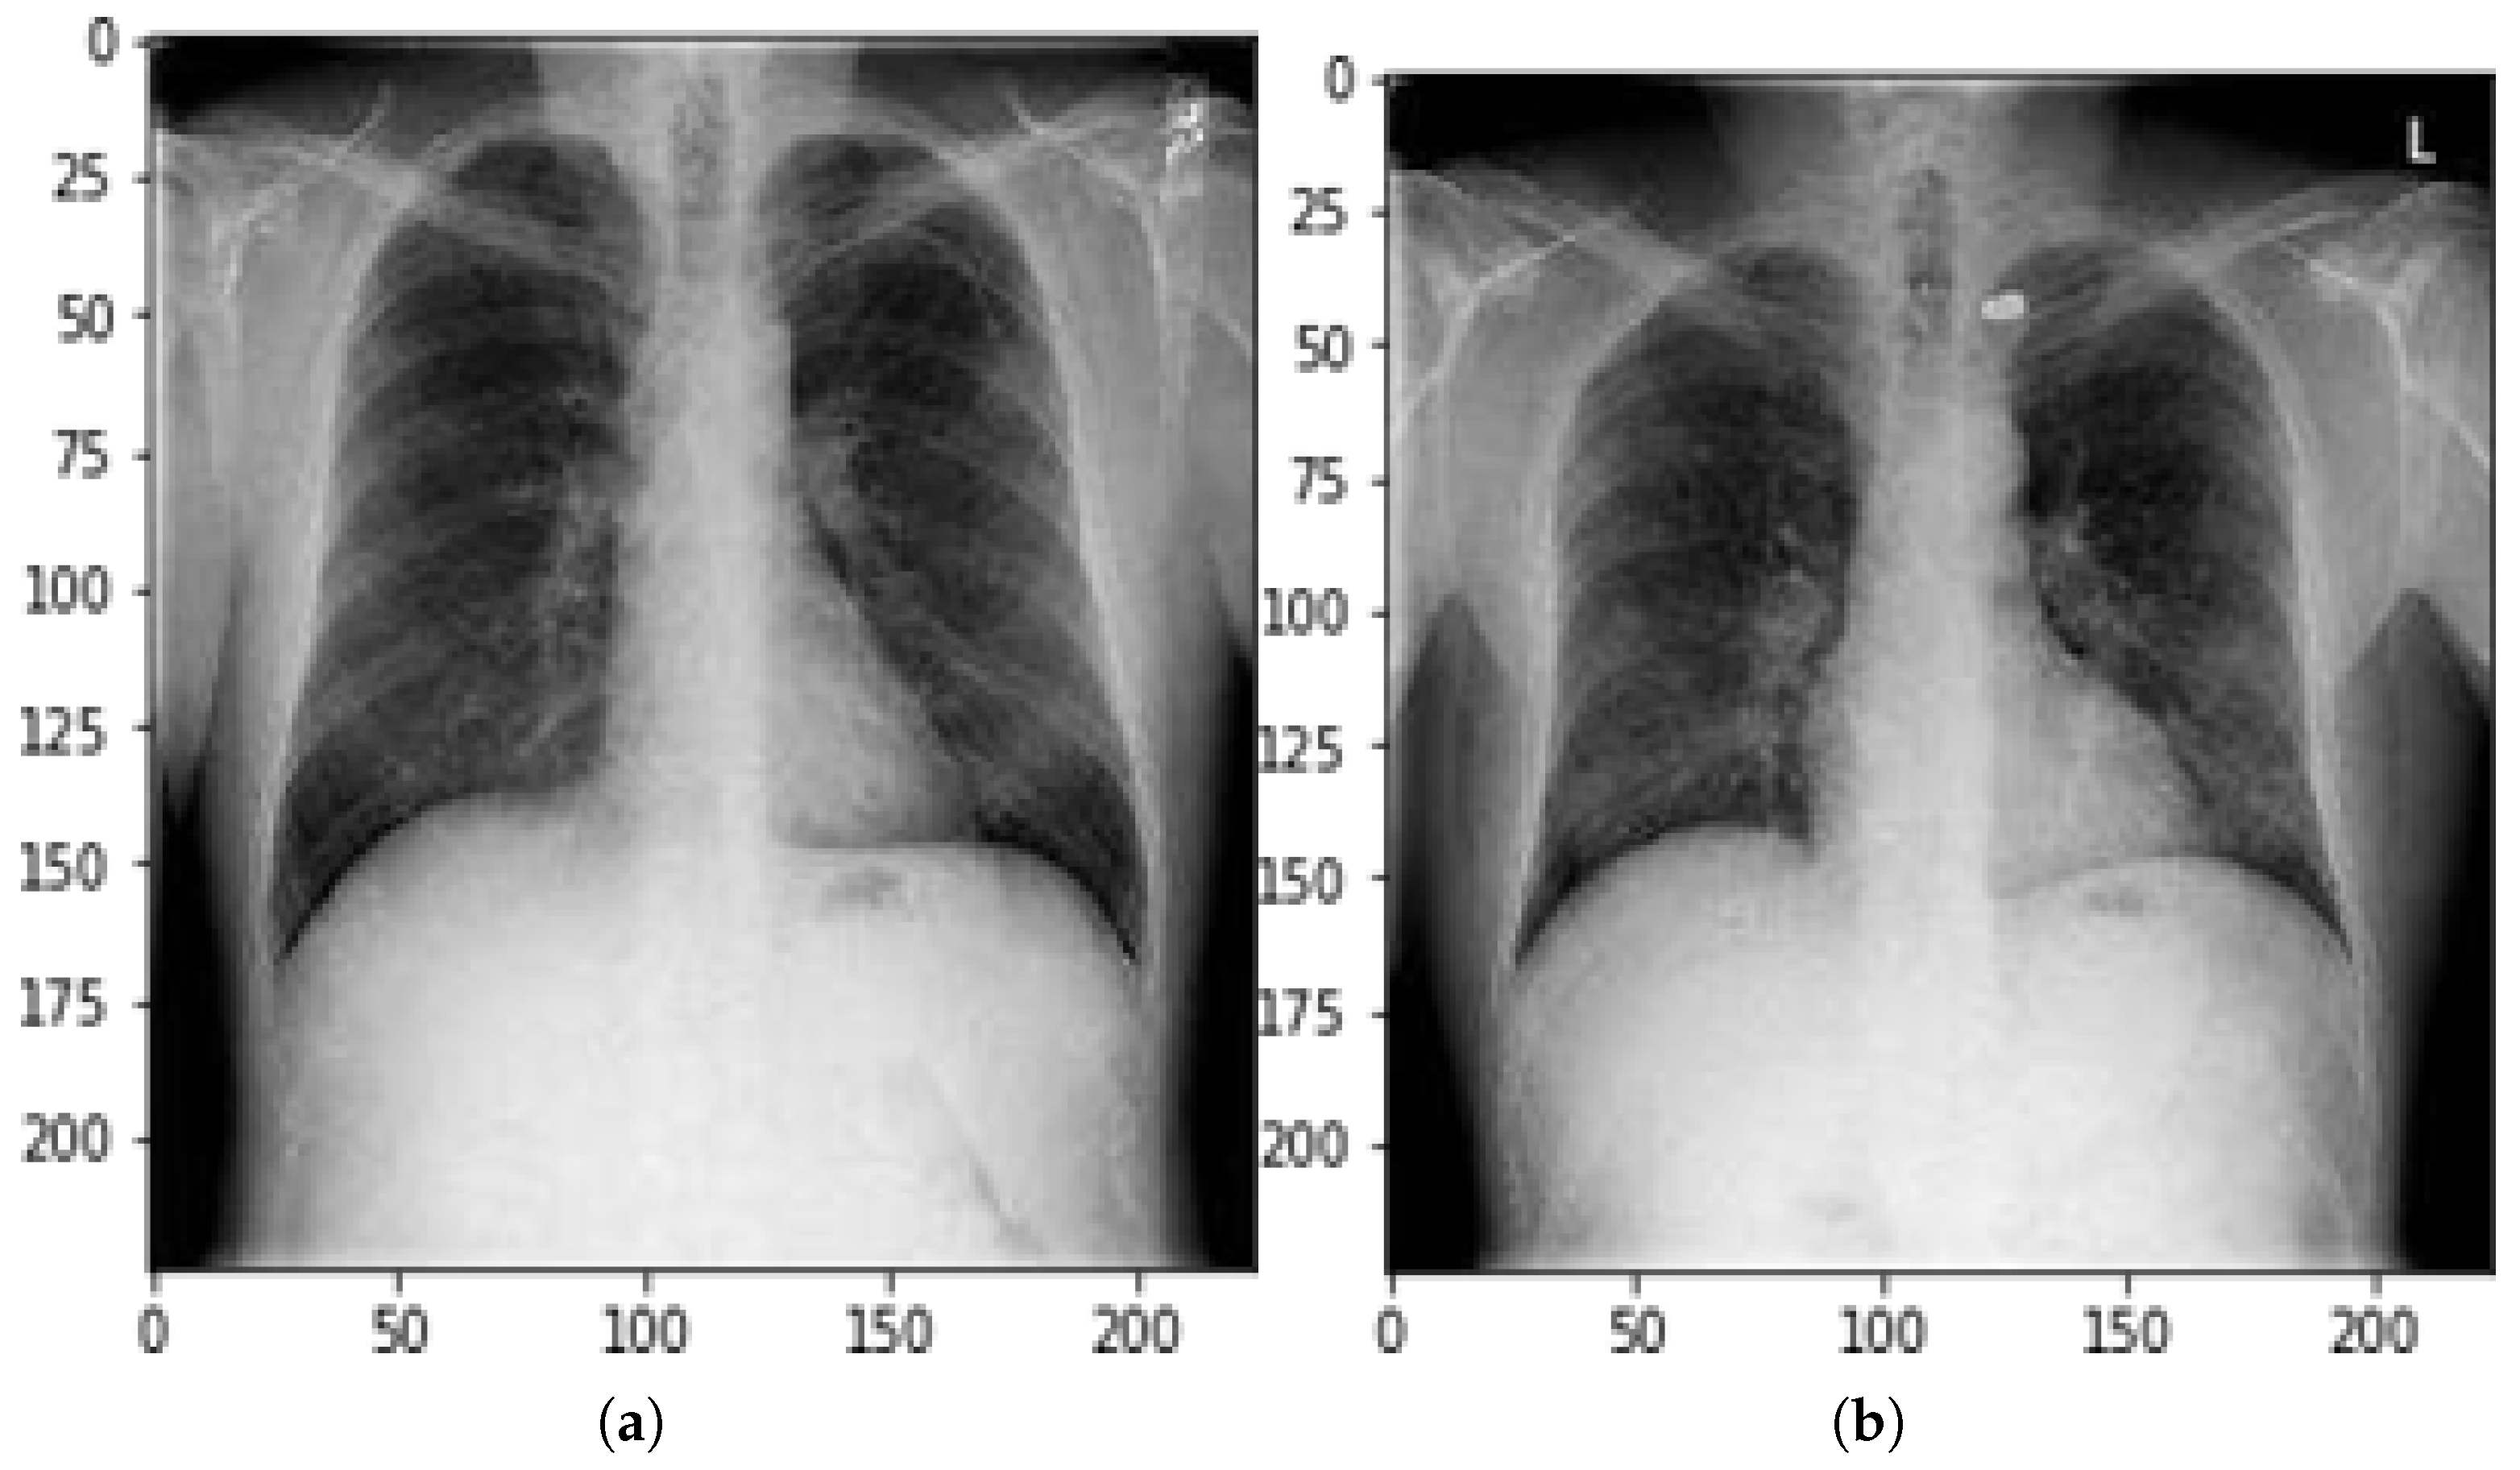

Figure 3. Classification classes. (a): Normal chest X-ray, prediction: 0.03418971; (b): Bullet implanted chest X-ray, prediction: 0.8629053.